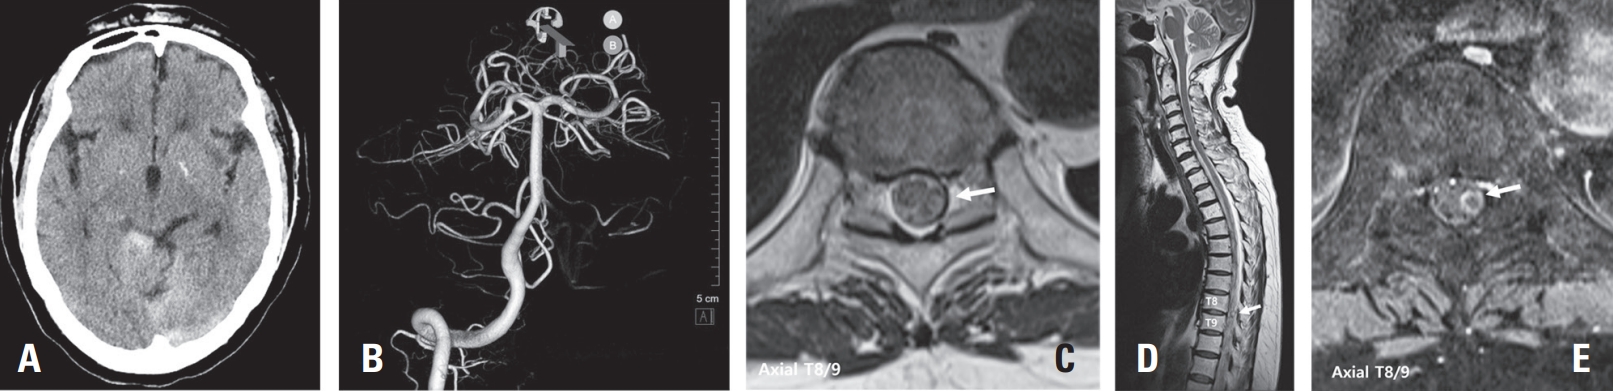

A 71-year-old female patient presented to a local clinic with sudden onset headache and back pain on the day of admission. A brain computed tomography (CT) scan performed at the local clinic diagnosed subarachnoid hemorrhage (SAH) in the basal cistern (Fig. 1A). 3-dimention CT brain angiography was conducted but failed to identify the source of the hemorrhage (Fig. 1B). Consequently, the patient was transferred to our hospital for further evaluation and management. Upon arrival, the patient complained of severe back pain. To investigate the potential spinal origin of the hemorrhage, a contrast-enhanced Magnetic Resonance Imaging (MRI) of the thoracic spine was performed. This revealed an abnormal intradural extramedullary heterogenous lesion located in the T8/9 level suspected as the source of bleeding (Fig. 1C, D, E). Immediately, spinal angiography of the thoracic spinal vascular lesion was performed. Spinal angiography revealed the fusiform aneurysm on a distal segment of a radiculopial artery of the left intercostal artery at left T9 (Fig 2A, B, C). However, the feeding artery was found to be too narrow, precluding endovascular procedures such as embolization.

Fig. 1.

(A) brain CT scan showing subarachnoid hemorrhage in the basal cisterns. It indicates acute bleeding. (B) 3-dimention reconstruction of CT brain angiography revealing no obvious aneurysmal source of hemorrhage in the cerebral vasculature. (C) Axial T2-weighted MRI at the T8/9 level. This image showing the intradural mass of heterogenous signal intensity in the spinal cord and surrounding structures (arrow). (D) Sagittal T2-weighted MRI of the thoracic spine showing extensive subdural hematoma extending from T1 to S1 level and a mass causing spinal cord compression at the T8/9 level (arrow). (E) Axial T1-weighted post-contrast MRI at the T8/9 level. A focal rim-enhancing lesion in the left intradural or subarachnoid space of the thecal sac at the T8/9 level (arrow).

Fig. 1. (A) brain CT scan showing subarachnoid hemorrhage in the basal cisterns. It indicates acute bleeding. (B) 3-dimention reconstruction of CT brain angiography revealing no obvious aneurysmal source of hemorrhage in the cerebral vasculature. (C) Axial T2-weighted MRI at the T8/9 level. This image showing the intradural mass of heterogenous signal intensity in the spinal cord and surrounding structures (arrow). (D) Sagittal T2-weighted MRI of the thoracic spine showing extensive subdural hematoma extending from T1 to S1 level and a mass causing spinal cord compression at the T8/9 level (arrow). (E) Axial T1-weighted post-contrast MRI at the T8/9 level. A focal rim-enhancing lesion in the left intradural or subarachnoid space of the thecal sac at the T8/9 level (arrow).